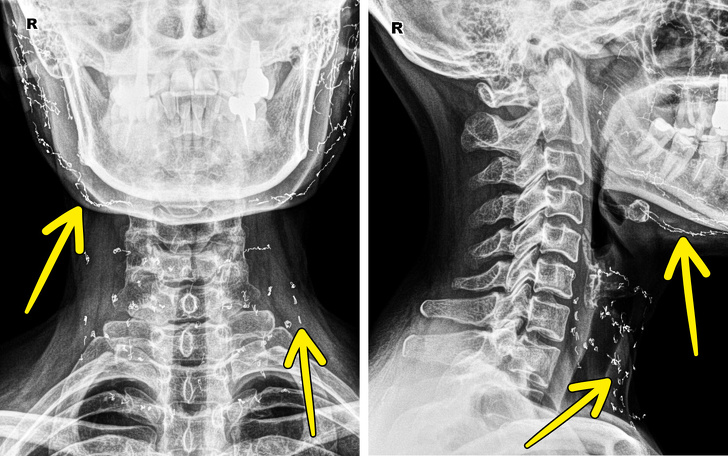

Ez egy olyan páciens röntgenképe, akinél jól látszik, hogy korábban aranyszálas arcfeszesítésen vett részt.